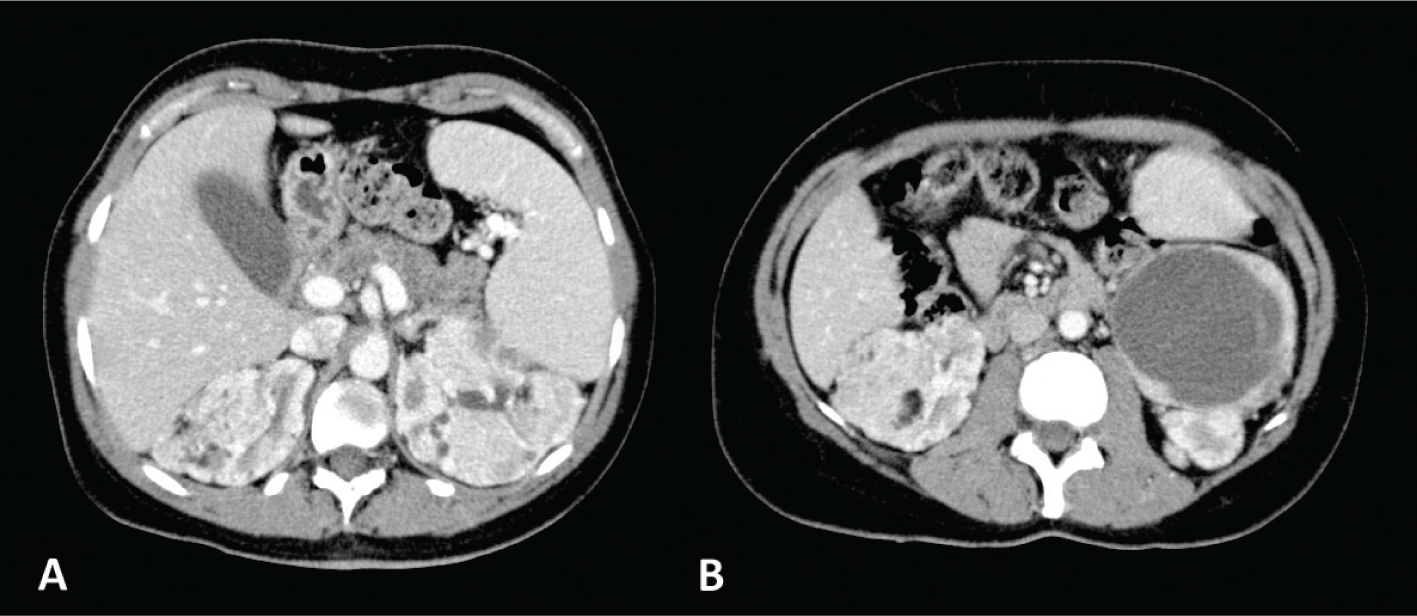

Classic AML is a subtype of triphasic AML. The typical characteristic of classic AML is the presence of abundant adipose tissue (11). This AML almost always appears markedly hyperechoic compared to the renal parenchyma. In addition, 21–33% of AMLs smaller than 3 cm show acoustic shadowing (58, 59). The fat present in AML can be identified on unenhanced CT with a region of interest (ROI) showing an attenuation less than −10 HU (Figure 3) (50, 60, 61). The CT features of classic AML vary due to variable amounts of the three components present in the lesion (11). Furthermore, intralesional hemorrhage may be present, especially in tumors larger than 4 cm (62). MRI can be used to diagnose AML also by detecting fat cells; India ink artifact visible with a loss of signal at the boundary between the mass and the renal parenchyma is indicative of AML (52).

Fig 3

Figure 3. Unenhanced CT axial scan of the abdomen (A and C) and CT of the abdomen during arterious phase (B and D) of a 53-year-old woman showing the presence of classic AMLs, recognizable by the adipose component of the lesion.